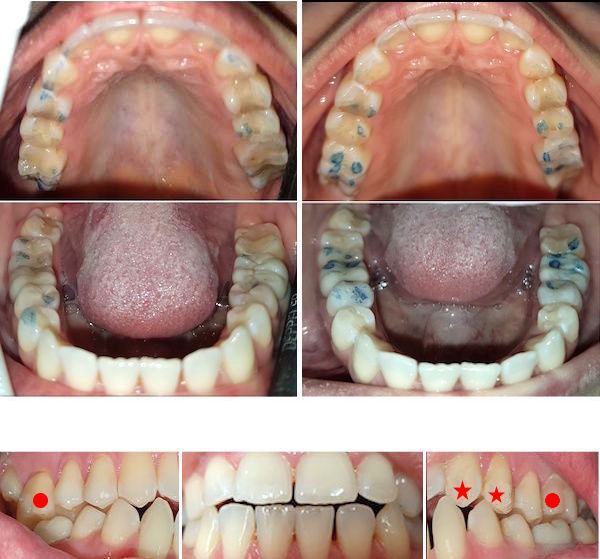

24-jähriger Patient (17.11.2025 / 8888)

Anamnese: Der Patient musste wegen einer kieferorthopädischen Behandlung 4+4 ziehen und 765+567 nach vorne verschieben lassen. Deshalb ist eine Minderbelastung des Kauzentrums 6-6 entstanden. Um besser kauen zu können, hat er nur noch links gebissen. Dabei ist aber +7 elongiert und ein Vorkontakt auf +-7 entstanden, der ihn störte. Er hat deshalb schon fünf verschiedene Knirscherschienen erhalten.

Therapie: Die mesialen Höcker des Zahnes 6- konnten ganz einfach mit Komposit erhöht werden.

Das Kaugefühl war dann sofort besser.

In der nächsten Sitzung wird auch noch der Zahn 5- erhöht, um das Kauzentrum noch etwas mehr zu vergrössern.

Vorbehalt: das Kaugefühl ist gut geblieben.

Der Patient hatte nach der kieferorthopädischen Behandlung kein gutes Bissgefühl. Die Anfärbung zeigt, dass die wichtigsten Molaren 6-6 fast nicht belastet werden.

Mit Komposit wurde auf die Molaren 76-6 je ein Witzgall-Höcker aufgesetzt. Diese befinden sich nicht am gewöhnlichen Ort, sondern dort, wo sie den Biss am besten unterstützen. Bei der kieferorthopädischen Behandlung mussten die oberen Molaren etwas nach vorne verschoben werden und passten deshalb nicht mehr gut zu den unteren.